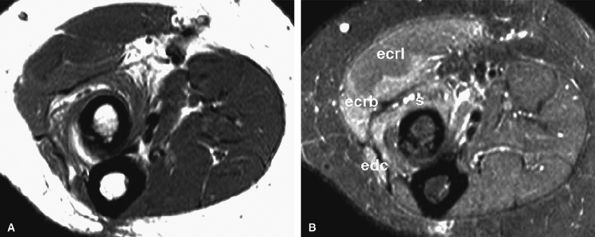

FIGURE 12.35 ● Posterior interosseous nerve syndrome. Axial T1-weighted (A) and fat-suppressed T2-weighted (B) images at the proximal forearm show atrophy and edema of the supinator and extensor musculature. The extensor carpi radialis longus, which is not innervated by the posterior interosseous nerve, is not involved. s, supinator; edc, extensor digitorum communis; ecrb, extensor carpi radialis brevis; ecrl, extensor carpi radialis longus.

|